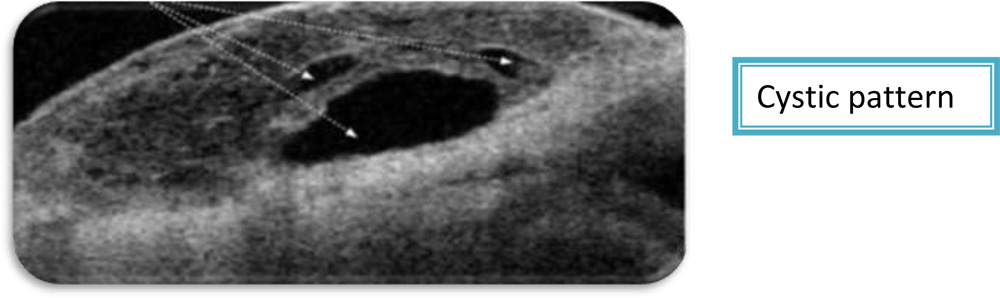

3.Bleb pattern– Three types of bleb patterns were noted-Diffuse, cystic and non functioning.

a) Cystic blebs were composed of a large subconjunctival hyporeflective space with multiloculated fluid collections of varying size and intensity. The blebs were covered by a thin layer of conjunctiva.